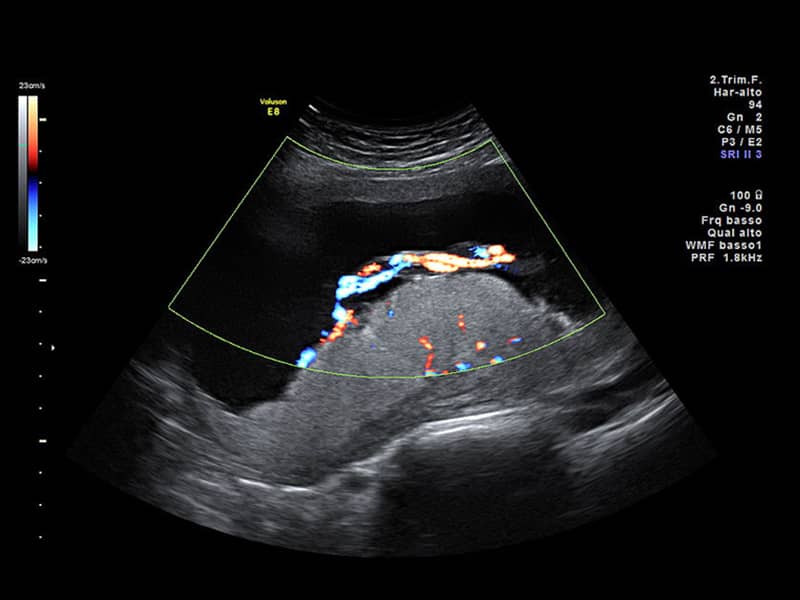

استعمال دخانیات یا تنباکو - قبل از آزمایش از سیگار کشیدن یا جویدن تنباکو خودداری کنید زیرا نیکوتین موجود در این مواد ممکن است باعث انقباض عروق شود که ممکن است نتایج آزمایش را به ویژه در مورد داپلر رنگی زنان و زایمان تغییر دهد.

سپس یک مبدل یا کاوشگر بر روی پوست ناحیه شکم- لگن حرکت می کند که امواج صوتی با فرکانس بالا را به قسمت های بدن مادر و جنین می فرستد. این امواج صوتی به عقب منعکس می شوند و توسط دستگاه اولتراسوند ضبط می شوند و به تصویر یا نمودار تبدیل می شوند. این تصاویر توسط سونوگرافیک برای ارزیابی وضعیت شما تفسیر می شود.

این اسکن احتمالاً مهمترین اسکن تشخیصی است که در بارداری انجام می شود. جنین اندازه مناسبی برای ارزیابی همه اندام ها دارد تا سونوگرافیک ببیند که آیا کودک شما نقص آشکاری مانند اسپینا بیفیدا یا شکاف کام دارد یا خیر.

اگر نگران مشکلات کروموزومی هستید، این اسکن می تواند نشانگرهای ظریفی را شناسایی کند که ممکن است نشان دهد کودک شما در معرض خطر بیشتری برای این سندرم ها است. نمونههایی از این نشانگرها پوست ضخیم پشت گردن، مایع اضافی در کلیه ها، دست ها یا پاهای کوتاه ، نواحی روشن در قلب یا شکم یا کیست های مغز هستند.

هدف از اسکن آناتومی بررسی کامل کودک شما از سر تا انگشتان پا است. اندازه گیری های خاصی انجام می شود و اندام های قابل مشاهده یک به یک ارزیابی می شوند. ساختارهای اطراف بارداری مانند دهانه رحم، جفت، بند ناف و حجم مایع آمنیوتیک نیز ارزیابی می شوند.

سونو گرافی آنومالی مرحله دوم یا اسکن آنومالی یک روش بدون درد ، سریع ، غیر تهاجمی و ایمن است که برای تشخیص ناهنجاری های مادرزادی و ناهنجاری های رشد در جنین استفاده می شود. همچنین آسیب شناسی جفت را شناسایی می کند، به برنامه ریزی نحوه و زمان زایمان کمک می کند و ارزیابی می کند که آیا نیازی به ختم بارداری وجود دارد یا خیر.

ناهنجاری های جنینی مانند سندرم داون، آنسفالی، امفالوسل، نقایص مادرزادی قلب، شکاف لب، آژنزی کلیه را شناسایی می کند. کمک به ارزیابی آسیب شناسی جفت مانند جفت سرراهی، وازا سرراهی، جفت بتلور، جفت آکرتا.